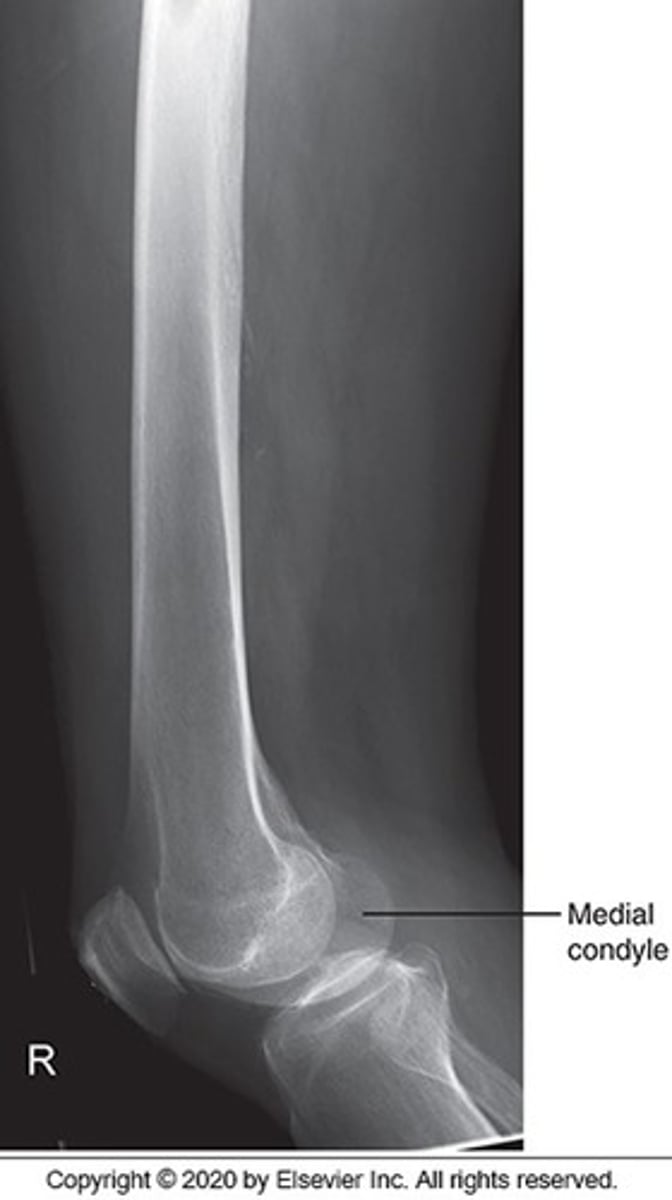

What positioning error is evident in the image below?

The lower limbs were not internally rotated

Identify this projection:

AP femur

AP pelvis

AP hip

Modified Cleaves